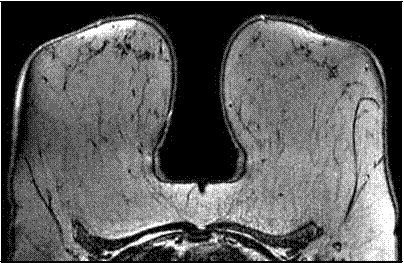

У женщин с инволютивным строением МЖ определялось выраженное увеличение толщины подкожной жировой клетчатки желез, железистый компонент не определялся, остаточная паренхима и соединительнотканные структуры обладали низкой интенсивностью сигнала и визуализировались в виде фиброзных тяжей идущих вдоль протоков (рис. 24).

Рисунок 24 — МР-маммограмма здоровой МЖ инволютивного типа. Определяется большое количество жировой ткани, железистая ткань не визуализируется.